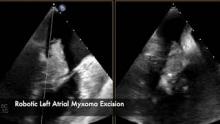

This video, narrated by Joel Dunning of Middlesbrough, UK, demonstrates a fascinating case of robotic left atrial myxoma excision.

Primary heart tumors are rare. This patient was found to have a large tumor in the left atrium, obstructing the mitral valve orifice, and the tumor was friable, which could have easily caused embolic stroke. In this case, a robotic surgical approach was used to remove the tumor completely. The patient's postoperative recovery was smooth. The robotic platform provides superior visualization and enhanced dexterity through keyhole incisions. Robotic surgery is an integral part of Dr Yan’s Minimally Invasive Cardiothoracic Surgery Program at the Royal Prince Alfred Hospital in Sydney, Australia.